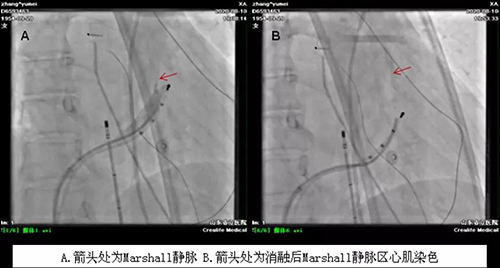

手术分两个步骤进行。第一步行Marshall 静脉无水乙醇化学消融,经下腔静脉将造影导管送至冠状窦内行选择性造影可见Marshall 静脉显影(图A,箭头处);沿导丝将OTW球囊送入Marshall 静脉内,扩张封堵后经中心腔将无水酒精注Marshall 静脉内,Marshall 静脉处心肌染色,提示造成二尖瓣峡部附近心房肌坏死(图A,箭头处)。

第二步行经典房颤消融“2C3L”术。经过Marshall 静脉化学消融,持续性房颤线性消融最难做的二尖瓣峡部消融变得异常简单,几个点即实现阻滞(见下图)。术中患者即恢复窦性心律。经过2小时的密切配合,成功完成手术,患者恢复窦性心律,生活质量极大改善。